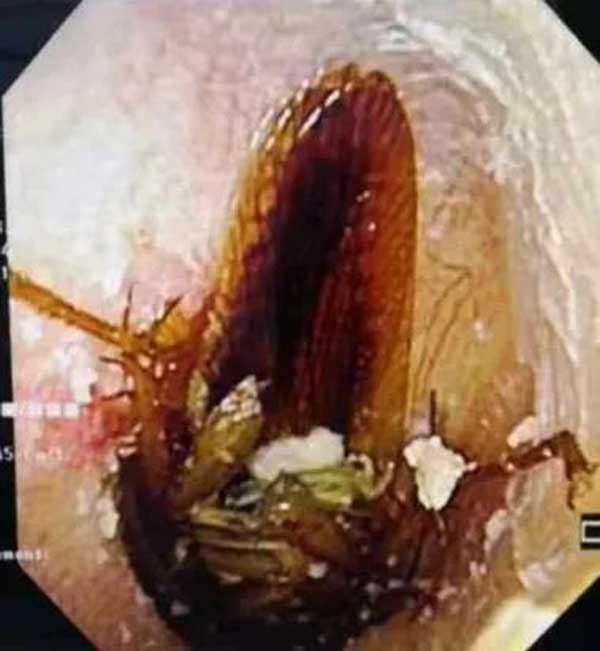

跑进耳朵里的小飞虫

次日一大早,3岁的阳阳就被妈妈带到了a片网站 耳鼻喉科。经过检查,跑进阳阳右耳朵里的是一只小飞虫,所幸虫子位置不深。在安抚了阳阳的情绪后,副主任李莉萍用镊子小心地夹出了一只指甲盖大小的活体飞虫。她说:“幸亏孩子没有用力掏耳朵,不然很可能造成鼓膜穿孔,影响孩子听力。”